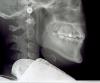

Alexandr dantist Опубликовано 26 мая, 2011 Поделиться Опубликовано 26 мая, 2011 .....ортопед говорит поставить коронку, хирург- удалить а гигиенист почистить Верьте ортодонту- по снимку вероятнее всего в вашем случае на второй зуб приходится нагрузка, которая ему не по силам. Причина- сосед,решивший сам не работать, а прикрыться за товарищем (не бегите ругать соседа-я про клык) Надо восстановить равновесие в системе-либо пропорциональным распределением нагрузки на все зубы-ортодонт. Либо вывести из контакта второй. (самый простой и не самый лучший вариант) Ссылка на комментарий

Alexandr dantist Опубликовано 26 мая, 2011 Поделиться Опубликовано 26 мая, 2011 точно! и это не единственное показание к исправлению прикуса для вас у вас же весь низ уехал... сколько вам лет? Ссылка на комментарий